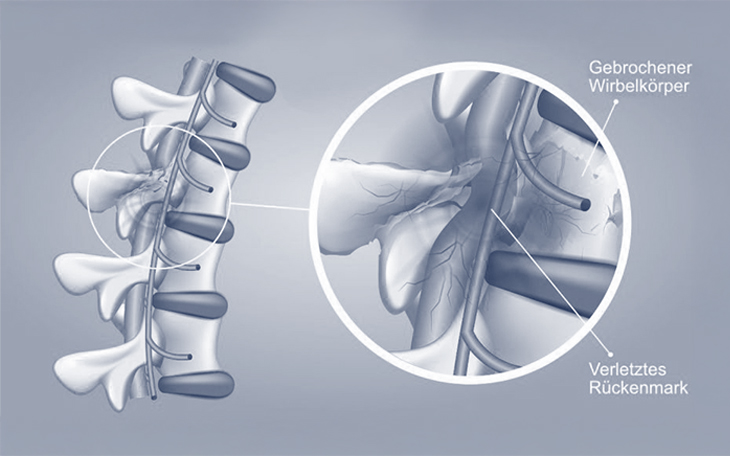

Eine thorakolumbale Fraktur bezeichnet einen Bruch eines Wirbelkörpers im Bereich der Brustwirbelsäule (thorakal) oder der Lendenwirbelsäule (lumbal).

Am häufigsten sind die Wirbel im Übergangsbereich zwischen Brust- und Lendenwirbelsäule betroffen – konkret zwischen T11 und L1. Diese Region verbindet die relativ unbewegliche Brustwirbelsäule mit der flexibleren Lendenwirbelsäule und ist daher besonders anfällig für Verletzungen. Während niedrigenergetische Traumata (z. B. leichte Stürze) eher die Bandscheiben schädigen, führen hochenergetische Unfälle – wie Verkehrsunfälle oder Stürze aus großer Höhe – häufiger zu Frakturen.

• Berstungsfraktur: Umfasst sowohl die vordere als auch die mittlere Säule. In schweren Fällen kann auch die hintere Säule betroffen sein. Knochenteile können nach hinten in den Spinalkanal treten und dort neurologische Strukturen gefährden.

Die Verletzungsmechanismen wirken abrupt und heftig – meist in Form einer Verdrehung oder stauchenden Krafteinwirkung, die innerhalb von Millisekunden zu einem Bruch des Knochens oder Riss der Bänder führen kann. Solche Ereignisse können zusätzlich das Rückenmark oder begleitende Nervenstrukturen schädigen. Eine daraus resultierende Rückenmarksverletzung ist häufig irreversibel und führt zu dauerhaften neurologischen Ausfällen.

Eine Rückenmarksverletzung (Spinal Cord Injury, SCI) zählt zu den schwerwiegendsten Verletzungen. Je nach Höhe und Ausmaß der Schädigung kann die Verletzung vollständig oder unvollständig sein. Typische Syndrome sind:

Eine komplette Rückenmarkverletzung führt in der Regel zu vollständigem Funktionsverlust unterhalb der Läsionsebene. Tetraplegie (Arme und Beine betroffen) und Paraplegie (nur Beine betroffen) sind je nach Läsionshöhe zu unterscheiden.

Die häufigste Ursache für Rückenmarksverletzungen sind Verkehrsunfälle. Weitere Ursachen sind Stürze, Gewalteinwirkung oder Sportunfälle. Plötzliche Krafteinwirkungen oder Verdrehungen des Rückens oder Nackens können Knochenbrüche, Bänderrisse oder Bandscheibenschäden verursachen, die wiederum das Rückenmark verletzen. Die Schädigung verläuft in zwei Phasen:

• Primäre Schädigung: Direkter mechanischer Schaden an Nerven, Blutgefäßen und Knochen.

• Sekundäre Schädigung: Entzündung, Schwellung, Blutungen und Durchblutungsstörungen führen zu fortschreitender Zellschädigung.